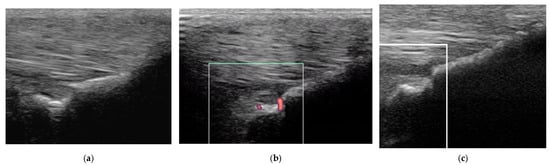

Figure 5. Twelve-year-old Warmblood mare; (a) B-mode transverse ultrasonographic image of the left forelimb lateral suspensory branch five days after injury. There is a well-defined hypoechoic region (red arrow) within the branch, and a hypoechoic region subcutaneously consistent with periligamentous oedema (blue arrow); (b) power Doppler image at the same level as (a). There is severe power Doppler signal. (c) Transverse power Doppler image one month after injury; there is no periligamentous oedema, the lesion in the branch is less well-defined and there is no power Doppler signal within the branch.

Figure 6. Twelve-year-old Warmblood mare with right hindlimb lameness and abduction of the limb during protraction. (a) Transverse, (b) longitudinal (distal to the right) and (c) transverse power Doppler images of the lateral branch of the suspensory ligament. There is a linear hyperechoic region causing acoustic shadowing. There is mild power Doppler signal localised around the hyperechoic region.

Figure 7. Transverse (left) and longitudinal (right) ultrasonographic images of the lateral branch of the suspensory ligament (SL) of a hindlimb of a 15-year-old purebred Spanish horse (PRE), acquired 2 weeks after injury, with a non-healing suspensory branch desmitis. The SL branch is enlarged with large hypoechoic regions and loss of long linear parallel echoes in the longitudinal image. There is also substantial subcutaneous echogenic tissue consistent with periligamentous fibrosis. Power Doppler signal was graded severe and persisted despite treatment. The horse was retired.

Figure 8. Longitudinal ultrasonographic images of the lateral branch of the suspensory ligament (SL) of a right forelimb of a four-year-old gelding (a,b) before treatment and (c) six months later; proximal is to the left. (a) There is loss of long linear parallel echoes in the dorsal aspect of the SL close to the enthesis. There is irregularity of the surface of the proximal sesamoid bone (PSB). (b) There was mild Doppler signal at the enthesis on the apex of the PSB. (c) At six months after treatment, a hypoechoic lesion persists, but there is no longer any power Doppler signal.